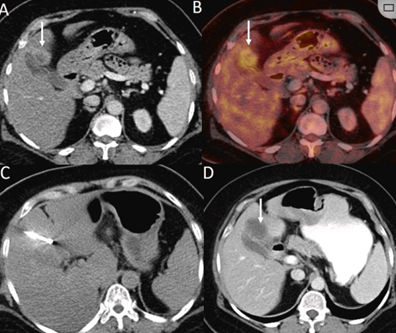

膽囊附近轉(zhuǎn)移灶(來自子宮頸癌)的冷凍消融術(shù)

(A)門靜脈期 CT 圖像顯示膽囊附近有病變(箭頭)。

(B) PET-CT 圖像顯示病變處(箭頭)。

(C) 手術(shù)過程中CT 顯示冷凍探針位于病灶內(nèi)。

(D)消融手術(shù)后 1 個(gè)月CT 顯示完全消融。